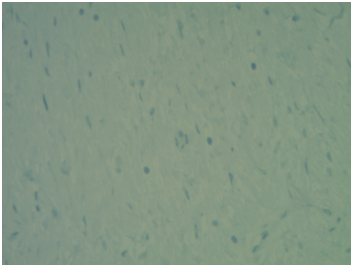

The pathological outcome for both tonsils was lymphoid hyperplasia. Gross examination for the left soft palate mass showed a pink-tan, soft, multilobulated, polypoid portion of smooth, shiny, rubbery tissue that measured 3.0 x 2.7 x 2.0cm. A sectioned portion of the specimen revealed multinodular, tan, rubbery, whorled cut surfaces (Figure 1 & 2). The initial pathologic diagnosis of the left soft palate mass was a benign plexiform lesion, however, the negative staining for S100 (Figure 3) and positive staining for smooth muscle actin (Figure 4) suggested myofibroblastic differentiation. Morphological features of the mass suggested a plexiform neurofibroma. Hence, combining the morphologic appearance with the findings from the Immunostains a new diagnosis favored plexiform leiomyoma.

Figure 3 Soft palate plexiform leiomyoma. (S100 Negative Stain).